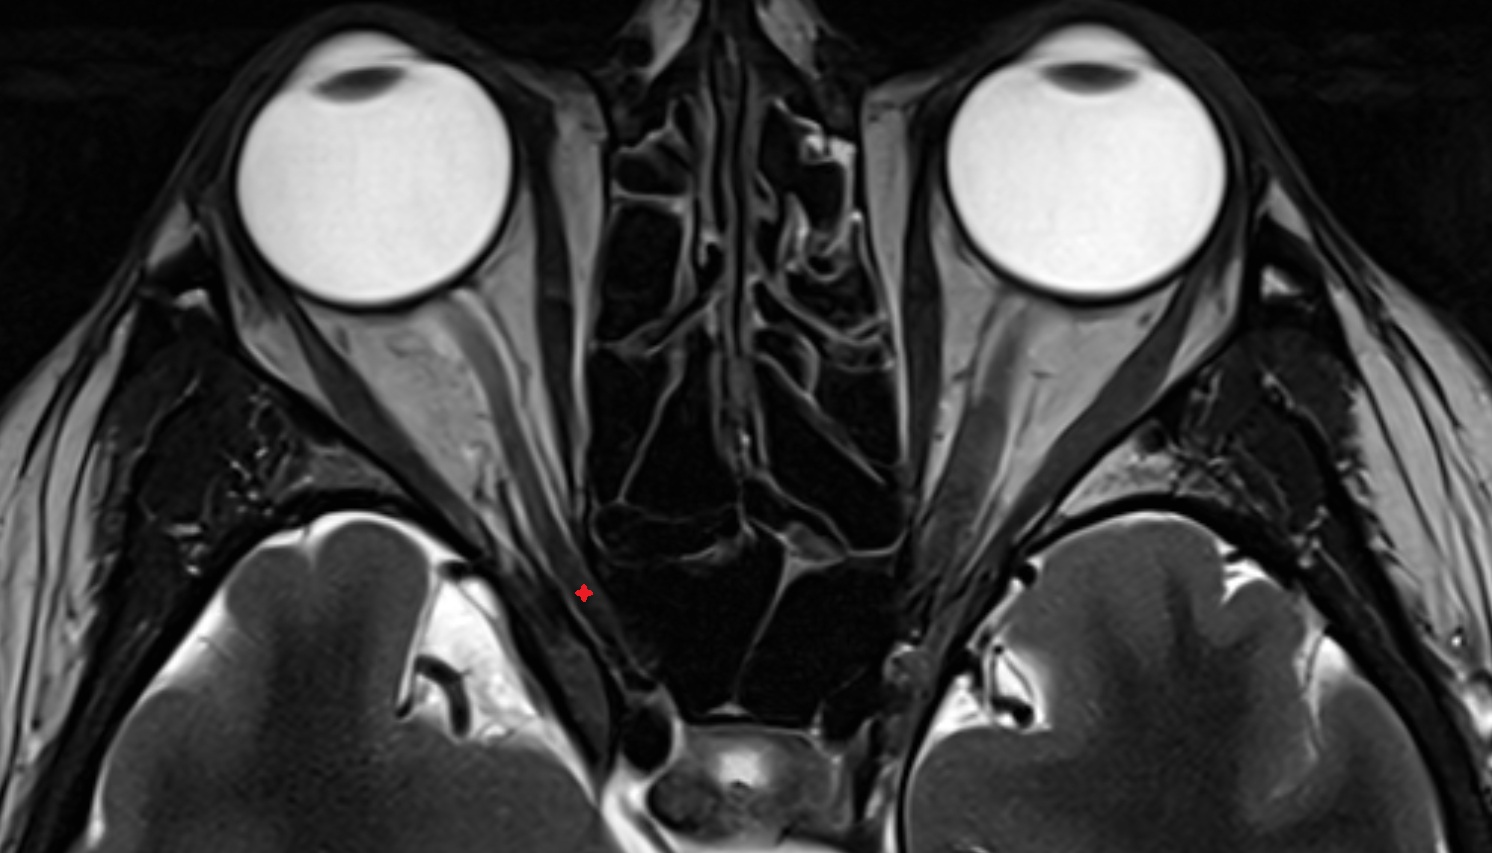

- Orbital part of optic nerve

- Retrobulbar fat

- Optic nerve sheath

- Subarachnoid space of optic nerve

- lens of the eye

- Cornea

- Iris

- Pupil

- Anterior chamber of eyeball

- Posterior chamber of eyeball

- Vitreous chamber of eyeball

- Sclera

- Choroid

- Retina